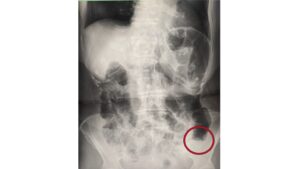

1ヶ月前から便秘と下痢を繰り返し出現した進行大腸癌の一例

2026-03-08